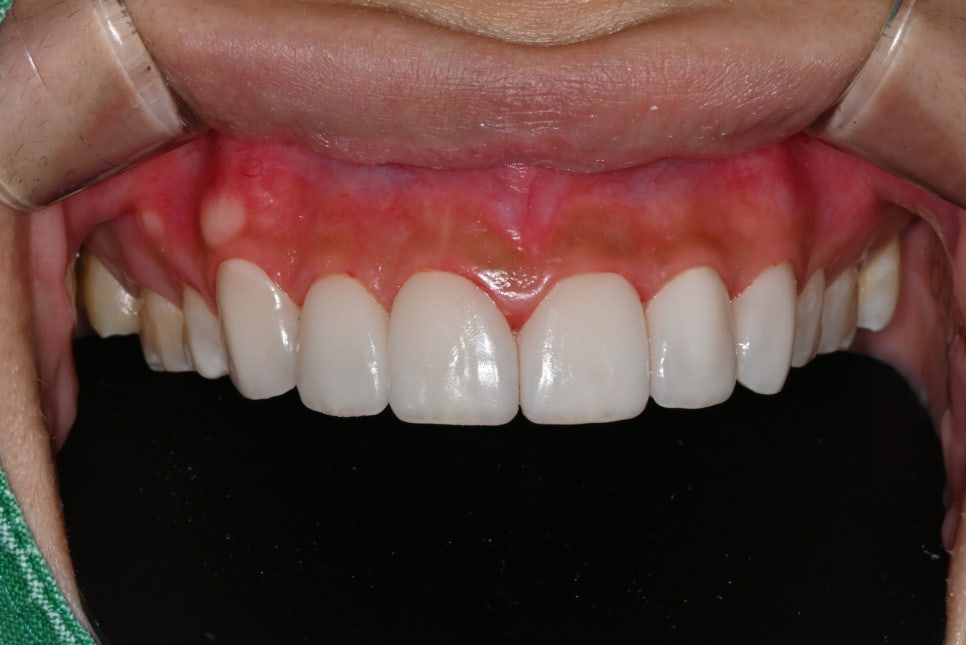

📸 After

– Brighter, smoother tooth tone

– Balanced front tooth line

– Natural shaping that harmonizes with the smile line

The patient said, “It’s not that my teeth just look prettier, it feels like my whole face has become brighter,” and shared that for the first time, she smiled widely without holding back when taking photos.